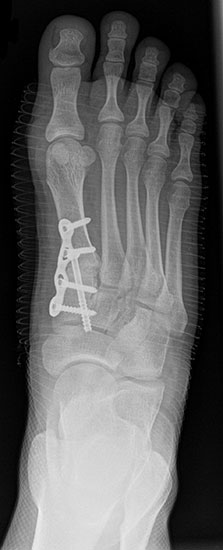

Bezüglich der Operationstechniken wird von früher häufig durchgeführten alleinigen Weich­teileingriffen am Großzehengrundgelenk aufgrund hoher Rezidivraten abgeraten 15. Die Operation nach Mc Bride mit lateralem Release, Exzision des lateralen Sesambeins, Abtragen der Pseudoexostose, Sehnenetransfer des M. adductor hallucis und mediale Kapselraffung zeigte unbefriedigende Mittel- und Langzeitergebnisse 16. Die Cerclage fibreux (mediale Kapselraffung) und das laterale Kapselrelease wird heute in Kombination mit einem knöchernen Eingriff angewendet. Bezüglich des Einsatzes von minimalinvasiven Operations­techniken vor Wachstumsabschluss liegen bisher keine Daten vor. Alle Osteotomien lassen sich nach Bedarf miteinander kombinieren. Es ist darauf zu achten, dass Osteotomien keine offenen Wachstumsfugen verletzen.

• Medial zuklappende Grundphalanxosteotomie nach Akin 17

• Subcapitale distale Chevron Osteotomie nach Austin 18

• Diaphysäre Osteotomie

• Scarf 19

• Ludloff 20

• Proximale Metatarsale I Osteotomien 21

• medial aufklappend – verlängernd

• lateral zuklappend – verkürzend

• bogenförmige Crescentic Osteotomie

• proximale Chevron Osteotomie

• proximale Verschiebeosteotomie

• medial aufklappende Cuneiforme I Osteotomie 1522

• Wachstumslenkung: Hemiepiphysiodese der lateralen Basisfuge am Metatarsale I  23

• Nach Schluss der Wachstumsfugen: TMT I Arthrodese nach Lapidus 2425